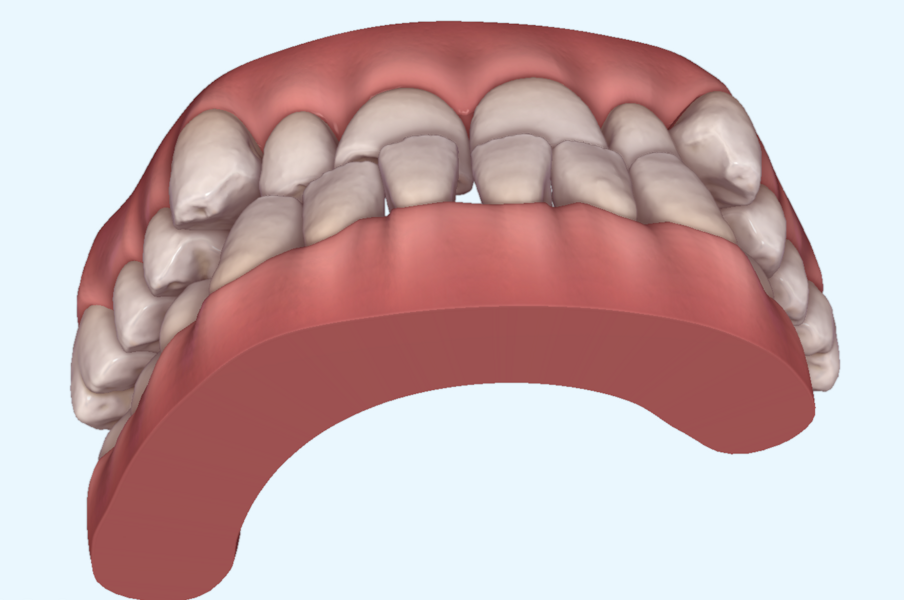

This patient, like all patients requiring interdisciplinary rehabilitation, had to first undergo periodontal treatment and caries restoration (Fig. 17). At the same time, it was important to rehabilitate swallowing with Froggymouth and relax the masticatory muscles and relieve the TMJs with an occlusal device. We could then study the orthodontic treatment plan using Invisalign ClinCheck (Align Technology) and showed the treatment plan to the interdisciplinary team and to the patient (Fig. 18). We were then able to create the correct sequence of orthodontic treatment, bone augmentation and implant surgery needed for the posterior edentulous spaces.

After the first phase of aligner treatment, we had achieved better inter-arch coherence, better maxillary arch expansion, and some space for improving the anterior tooth proportions restoratively (Fig. 19). We then temporarily restored the anterior teeth directly with composite, closing the spaces, improving the tooth proportions and further increasing the maxillary arch expansion (Fig. 20). We used restorative arch expansion to reduce the orthodontic destabilisation of the teeth to achieve the correct inter-arch coherence and retain the teeth in the cortical bone.38 A refinement aligner phase was undertaken to improve the final alignment of the gingival zenith and to improve the inter-arch coherence (Fig. 21). The periods of the first orthodontic phase and of the refinement were used to augment the mandibular and maxillary bone and to place the implants (Fig. 22). At the end of the orthodontic treatment, the case was finalised with ceramic veneers in the anterior area and temporary restorations on the implants in the posterior area (Figs. 23–26).